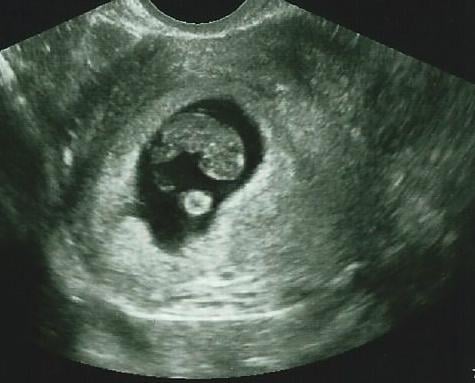

Below is a collection of prenatal ultrasound pictures from the Imaging Technology News (ITN) archive. Use the arrows to click through the image gallery. It includes transvaginal ultrasound images and fetal echocardiogram images. Fetal imaging is referred to by many names, including pregnancy sonograms, pregnancy ultrasound, endovaginal ultrasound, obstetric ultrasound, OB ultrasound, baby ultrasound, prenatal ultrasound. Fetal heart ultrasound is also called baby echo or prenatal echo.